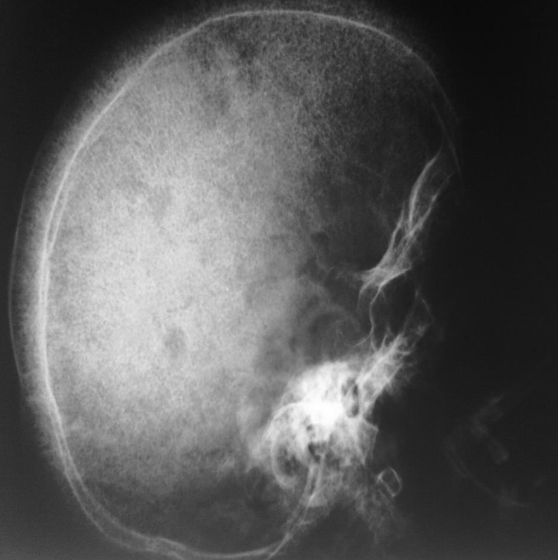

- Thalassemia

- Skull x-ray

- Hair on end appearance